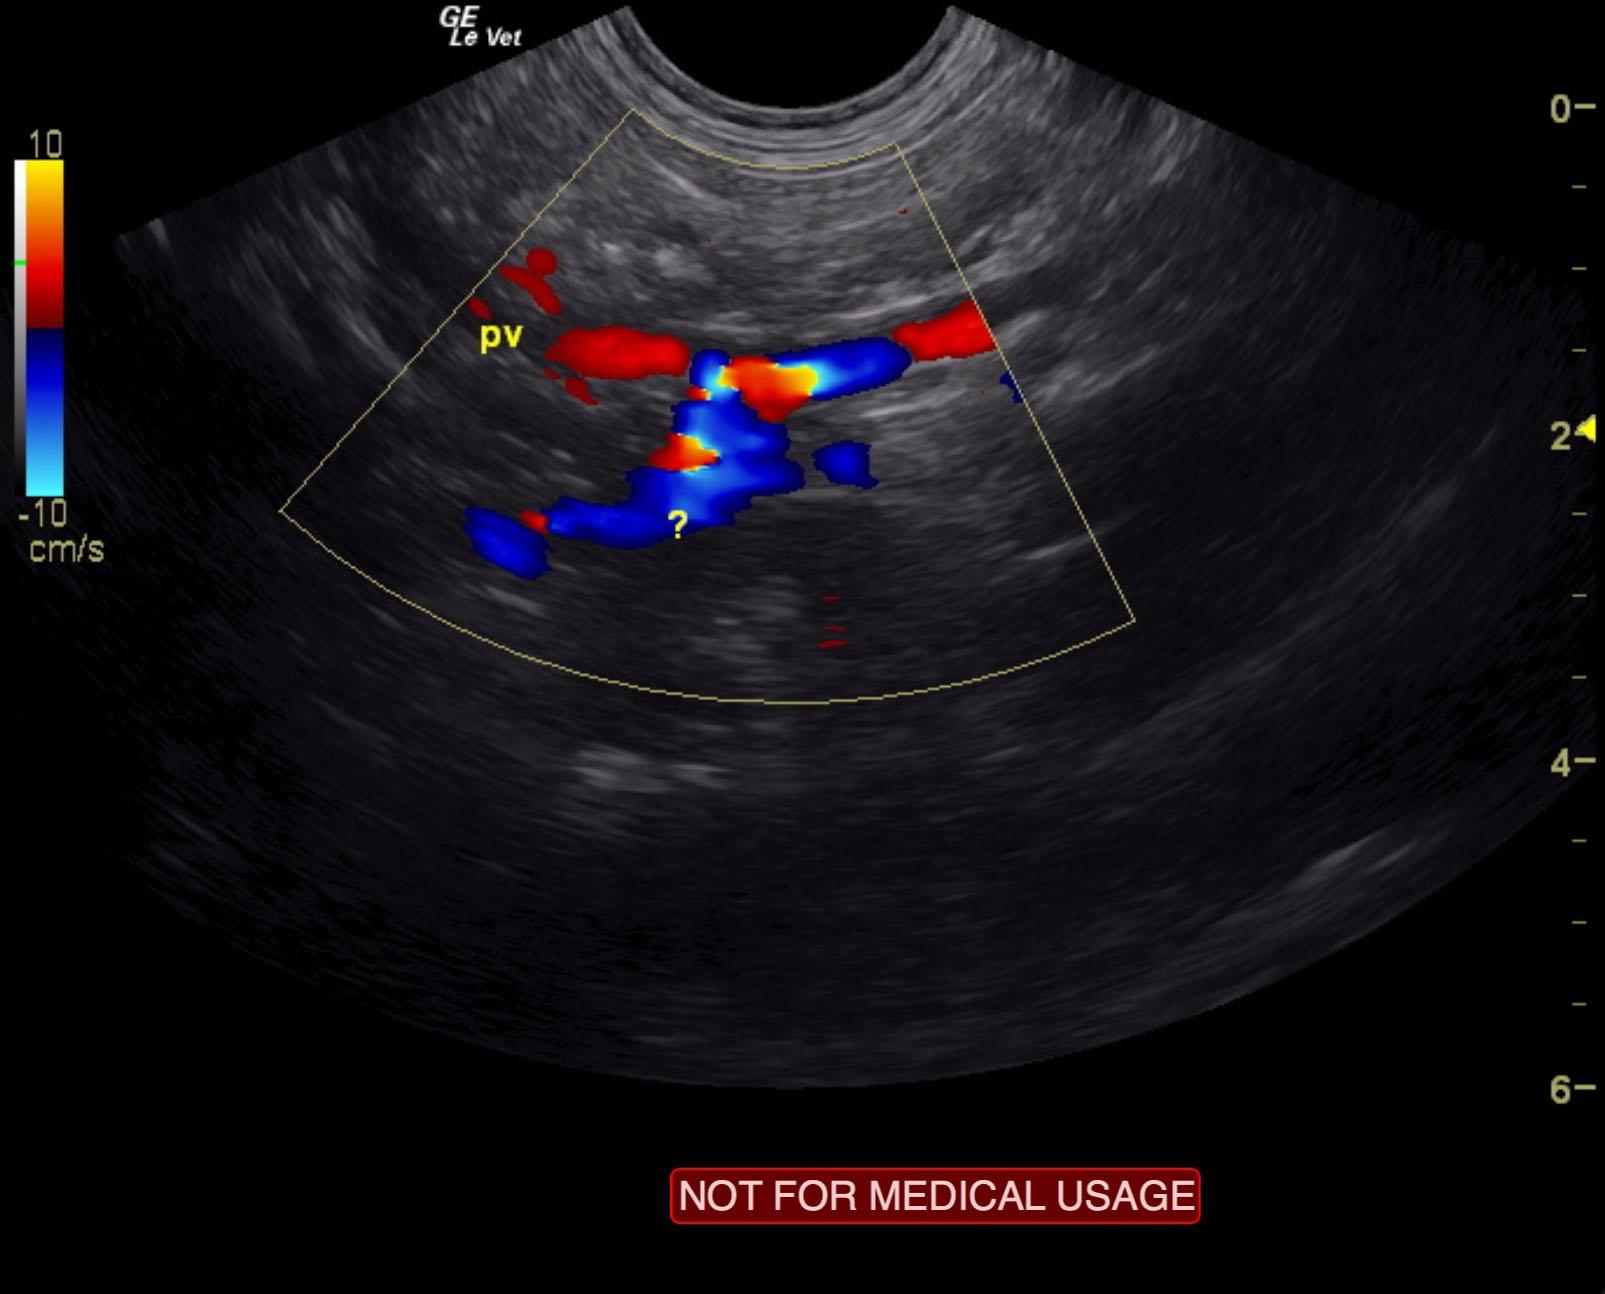

Extrahepatic portosystemic shunt, likely splenoazygos. Microhepatica.

The liver was significantly subnormal in size at 2.1 cm in short axis. A splenazygous shunt was noted in this patient and measured 0.85 cm in width and approximately 1.8 cm in length prior to entering dorsally into the vena cava. The pre-shunt portal vein measured 0.5 cm. Vena cava after the shunt measured 0.5 cm, and the aorta was 0.6 cm. Residual portal vein 0.3 cm. It appears that the shunt exits the splenic entry to the portal vein and creates a “double aorta” appearance cranial to the diaphragm, which is most consistent with a splenoazygos shunt. Hepatic parenchyma was hypovascular and relatively uniform with slightly increased portal markings. Concurrent inflammatory hepatopathy is likely along with the extrahepatic portosystemic shunt. The gallbladder was unremarkable.